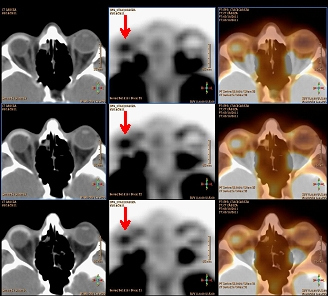

Posteriormente, en mayo/2011 se solicita nuevo 18F-FDG PET-TC de control evolutivo, donde se observó como único hallazgo de interés, un acúmulo hipermetabólico focal localizado en el interior de la prótesis ocular derecha, en probable relación con actividad inflamatoria debida al tejido de granulación que infiltra la prótesis, no sugestiva de malignidad (fig. 1B). En octubre/2011 se vuelve a solicitar nuevo 18F-FDG PET-TC de control donde se comprueba la persistencia del acúmulo focal descrito previamente en la prótesis ocular derecha (fig. 2), aunque de menor intensidad relativa.

La captación de 18F-FDG en la prótesis de MEDPOR observada a los 17 meses de su colocación es menor a la registrada a los 12 meses, lo cual sugiere una disminución progresiva de la actividad metabólica celular. A la vista de estos hallazgos, es posible que la 18F-FDG PET-TC pueda jugar un papel importante para investigar la vascularización de la prótesis de MEDPOR y podría representar una técnica de imagen alternativa a la RM en la evaluación de estos pacientes(7); sin embargo son necesarios estudios seriados y controlados para confirmar su utilidad.